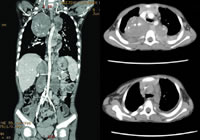

胸腹部CT:神经母细胞瘤,累及双侧后纵隔、肾上腺、膈肌脚、腹膜后及椎管内,局部肋骨破坏。

本病例患儿为学龄前男童,急性发病,临床表现除了间断发热、骨痛伴乏力外,有多汗、消瘦、苍白和心率快等儿茶酚胺代谢率增高症状。影像学检查提示病灶广泛,双侧后纵隔紧贴脊柱两侧缘及肾上腺、膈肌脚、腹膜后可见团块状占位性病变,病变通过扩张的椎间孔进入上胸椎椎管内。核素骨扫描提示多发骨代谢异常,骨髓细胞学检查提示骨髓侵犯。NSE、尿VMA、LDH明显升高。NBL(Ⅳ期)诊断明确。

图1、图2 患儿初诊时影像学检查提示瘤灶广泛分布于后纵隔和腹膜后